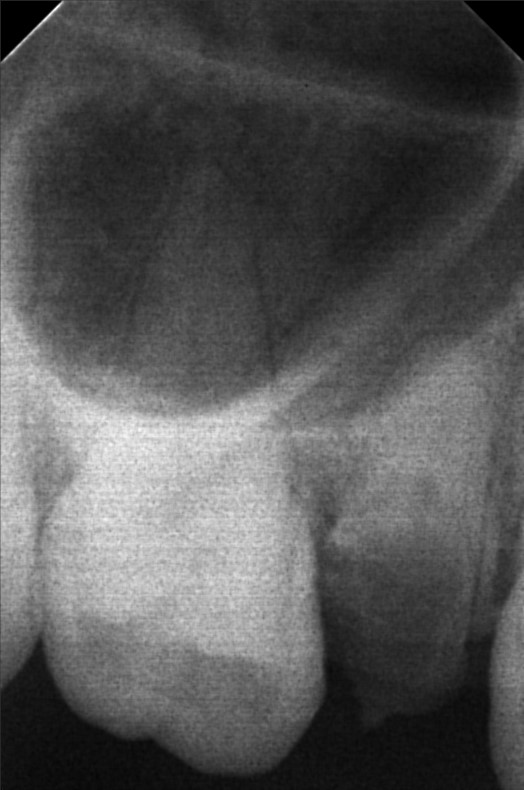

Edit Record Check our patient data records. Add patient information Patient Info Profile picture Last Name First Name Middle Name Birthdate Age Street Barangay City Country Zip Code Contact number Email Procedure 06/30/23- Informed Consent Ortho Check Up OP Impression Soft tissue analysis Intraoral photograph PA Radiograph For exo #15 Informed pt regarding class 5 cases Referred for cephalometric radiograph For resto class 5 #23, #24, #25, #35, #13, #14 10/24/25 oral prophylaxis xray tooth extraction #15 for restoration: abrasion: #23, 24, 25, 26, 14, 33, 35, 36, 44 recession: #13, 12, 11, 21, 22, 34, 32, 43 File atecotech2i712f_f.jpeg File 2 atecotech2i18f6_f.jpeg File 3 atecotech2i2a08_f.jpeg File 4 atecotech2i6330_f.jpeg File 5 atecotech2i278f_f.jpeg File 6 atecotech2i5dba_f.jpeg File 7 File 8 File 9 File 10 File 11 File 12 File 13 File 14 File 15 File 16 File 17 File 18 File 19 File 20 Retain Record Retain Record Yes No Save Your Changes